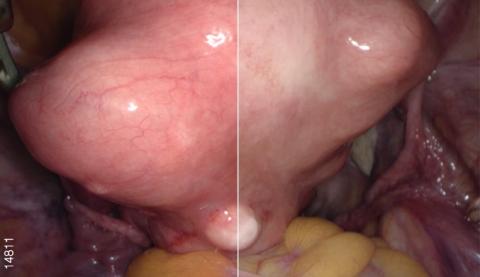

Видеоэндоскопическая система OLYMPUS VISERA 4K UHD обладает высококачественным изображением 4K и технологией узкоспектральной визуализации изображения NBI. Высокое разрешение позволяет визуализировать малейшие изменения в структуре тканей для ранней диагностики очагов воспаления и опухолей. Чем выше разрешение изображения, тем больше вероятность обнаружения очаговых изменений на ранней стадии. Процессор OTV-S400 позволяет получать изображения с разрешением 3840 х 2160 пикселей, что помогает увидеть значительно больше. Система поддерживает визуализацию в форматах 4K UHD (3840 × 2160) и Full 4K (4096 × 2160).

Видеосистема обладает сверхвысокой четкостью изображения. Точная настройка каждого слоя формирования изображения и идеальное устройство каждой функции означают оптимизацию изображений для хирургического вмешательства. Сверхвысокая четкость также обеспечивает улучшенную видимость изображения, которая позволяет хирургам проводить более безопасные и точные вмешательства.

Расширенная цветовая гамма

Видеопроцессор OTV-S400 создает расширенную цветовую гамму за счет использования формата цвета 4K (BT2020). Это обеспечивает насыщенную цветопередачу и соответствующие цвета для каждой области. Благодаря этому происходит упрощение определения границ тканей (жира, нервов, сосудов и т. п.) и улучшенная визуализация кровеносных сосудов и пораженных участков.